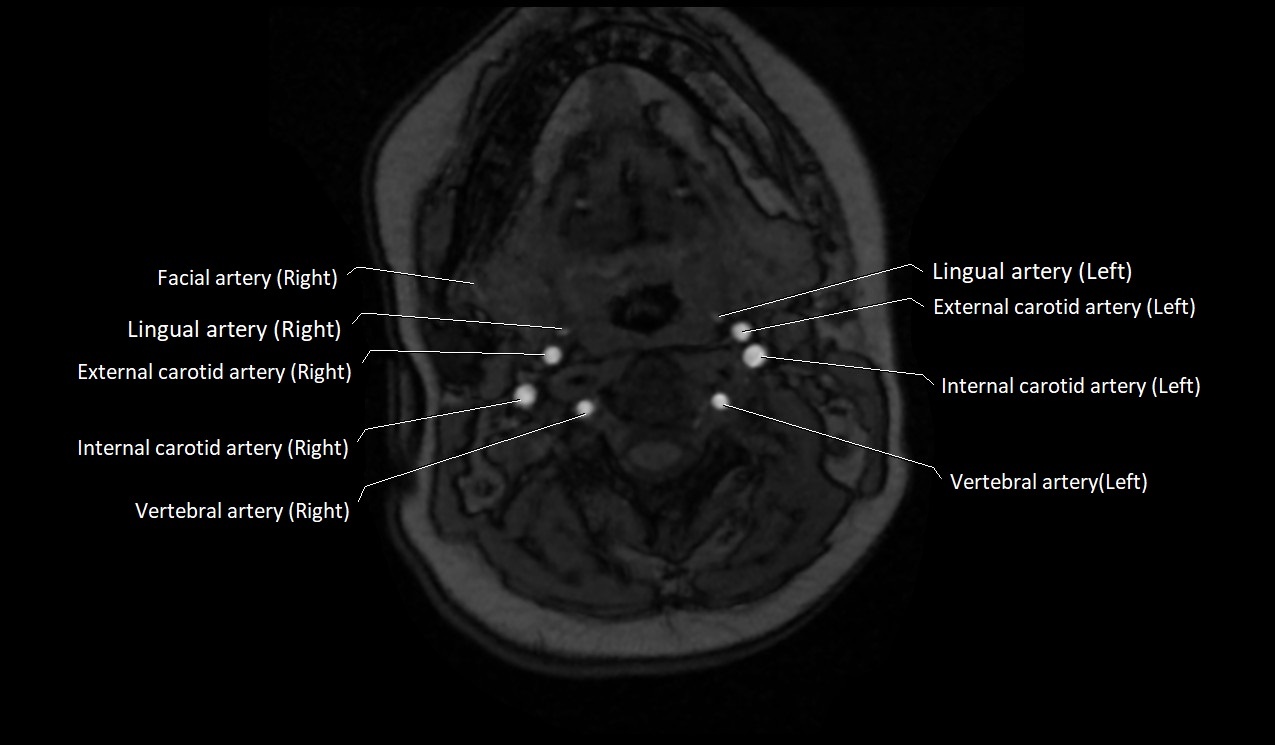

MRI images

image